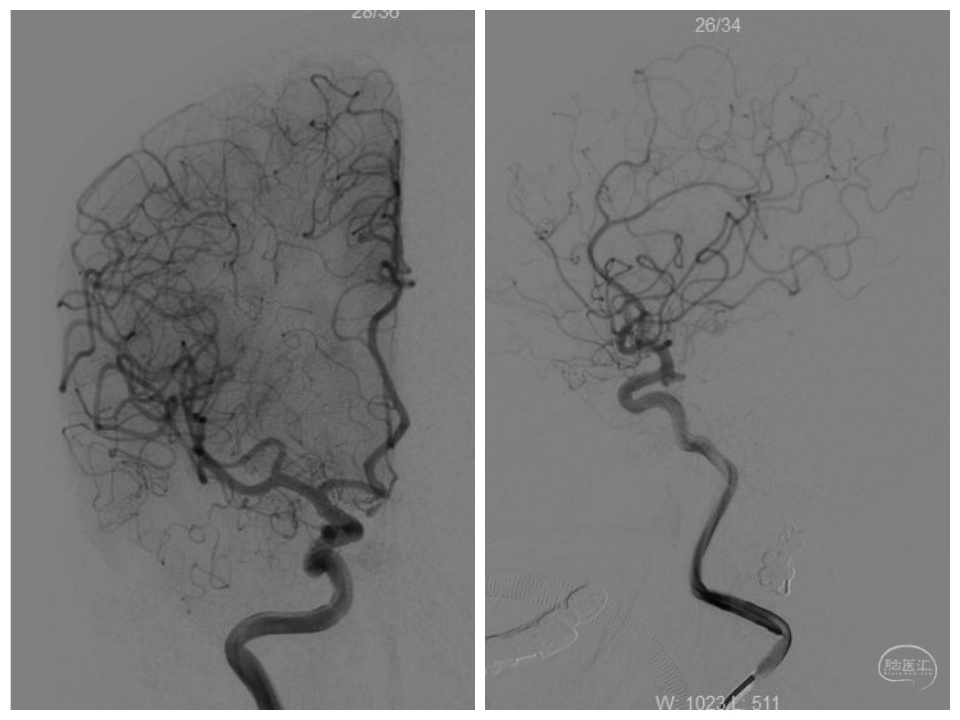

正侧位

两根微导管到位(箭头示微导管2),先经过微导管1植入一枚,三维Target3-4弹簧圈,不解脱。

再经过微导管2植入一枚,三维Target2-6弹簧圈。

再经过微导管2,植入一枚二维target2-4弹簧圈。

解脱第一枚弹簧圈,经过微导管1,继续填塞,二维Target2-4、APB1.5-4-3D-ES、APB1.5-2- HX-ES、APB1-4-3D-ES各一枚。

撤出微导管1,可见该微导管占据的缝隙,此处仍空虚。

造影

继续经过微导管2植入:APB1-3-3D-ES、二维Target1-2各一枚。